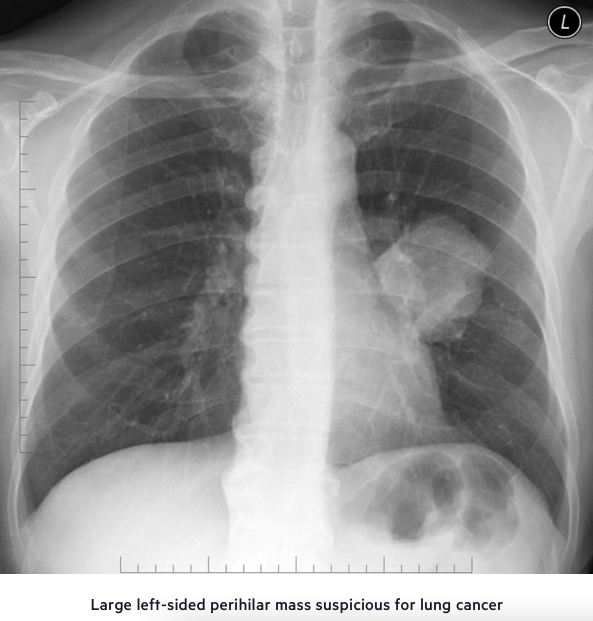

Chest X-Ray!!!!

• Focal lesion

• Pleural effusion

• Widened mediastinum due to enlarged hilar lymph nodes

• Diaphragm collapse